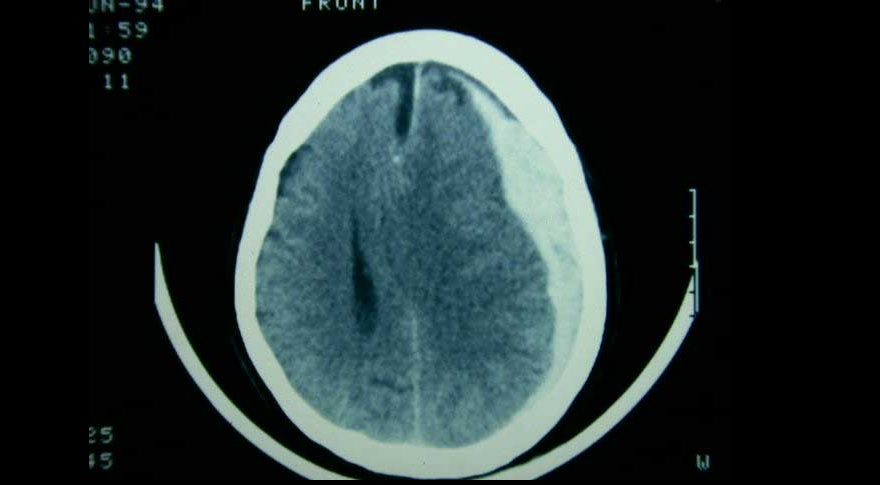

Embolización de la arteria meníngea media en el hematoma subdural subagudo o crónico

Tres ensayos clínicos exploran la utilidad de la embolización de esta arteria en el manejo del hematoma subdural subagudo o crónico, con miras a reducir la tasa de recurrencias y la necesidad de nuevas intervenciones. New England Journal of Medicine, 20 de noviembre de 2024.

Evacuación inicial o tratamiento conservador en el hematoma subdural agudo

El tratamiento de pacientes con hematoma subdural agudo difiere según el centro de tratamiento, debido a la variación en el abordaje preferido. Una estrategia de tratamiento que prefirió un enfoque agresivo de evacuación quirúrgica aguda sobre el tratamiento conservador inicial no se asoció con un mejor resultado funcional. The Lancet Neurology, 5 de mayo de 2022.

Eficacia y seguridad de la dexametasona en el hematoma subdural crónico

Un ensayo clínico mostró que el corticoide se asoció a peores resultados clínicos a los seis meses en comparación con placebo, pero con menor cantidad reoperaciones. New England Journal of Medicine, 16 de diciembre de 2020.